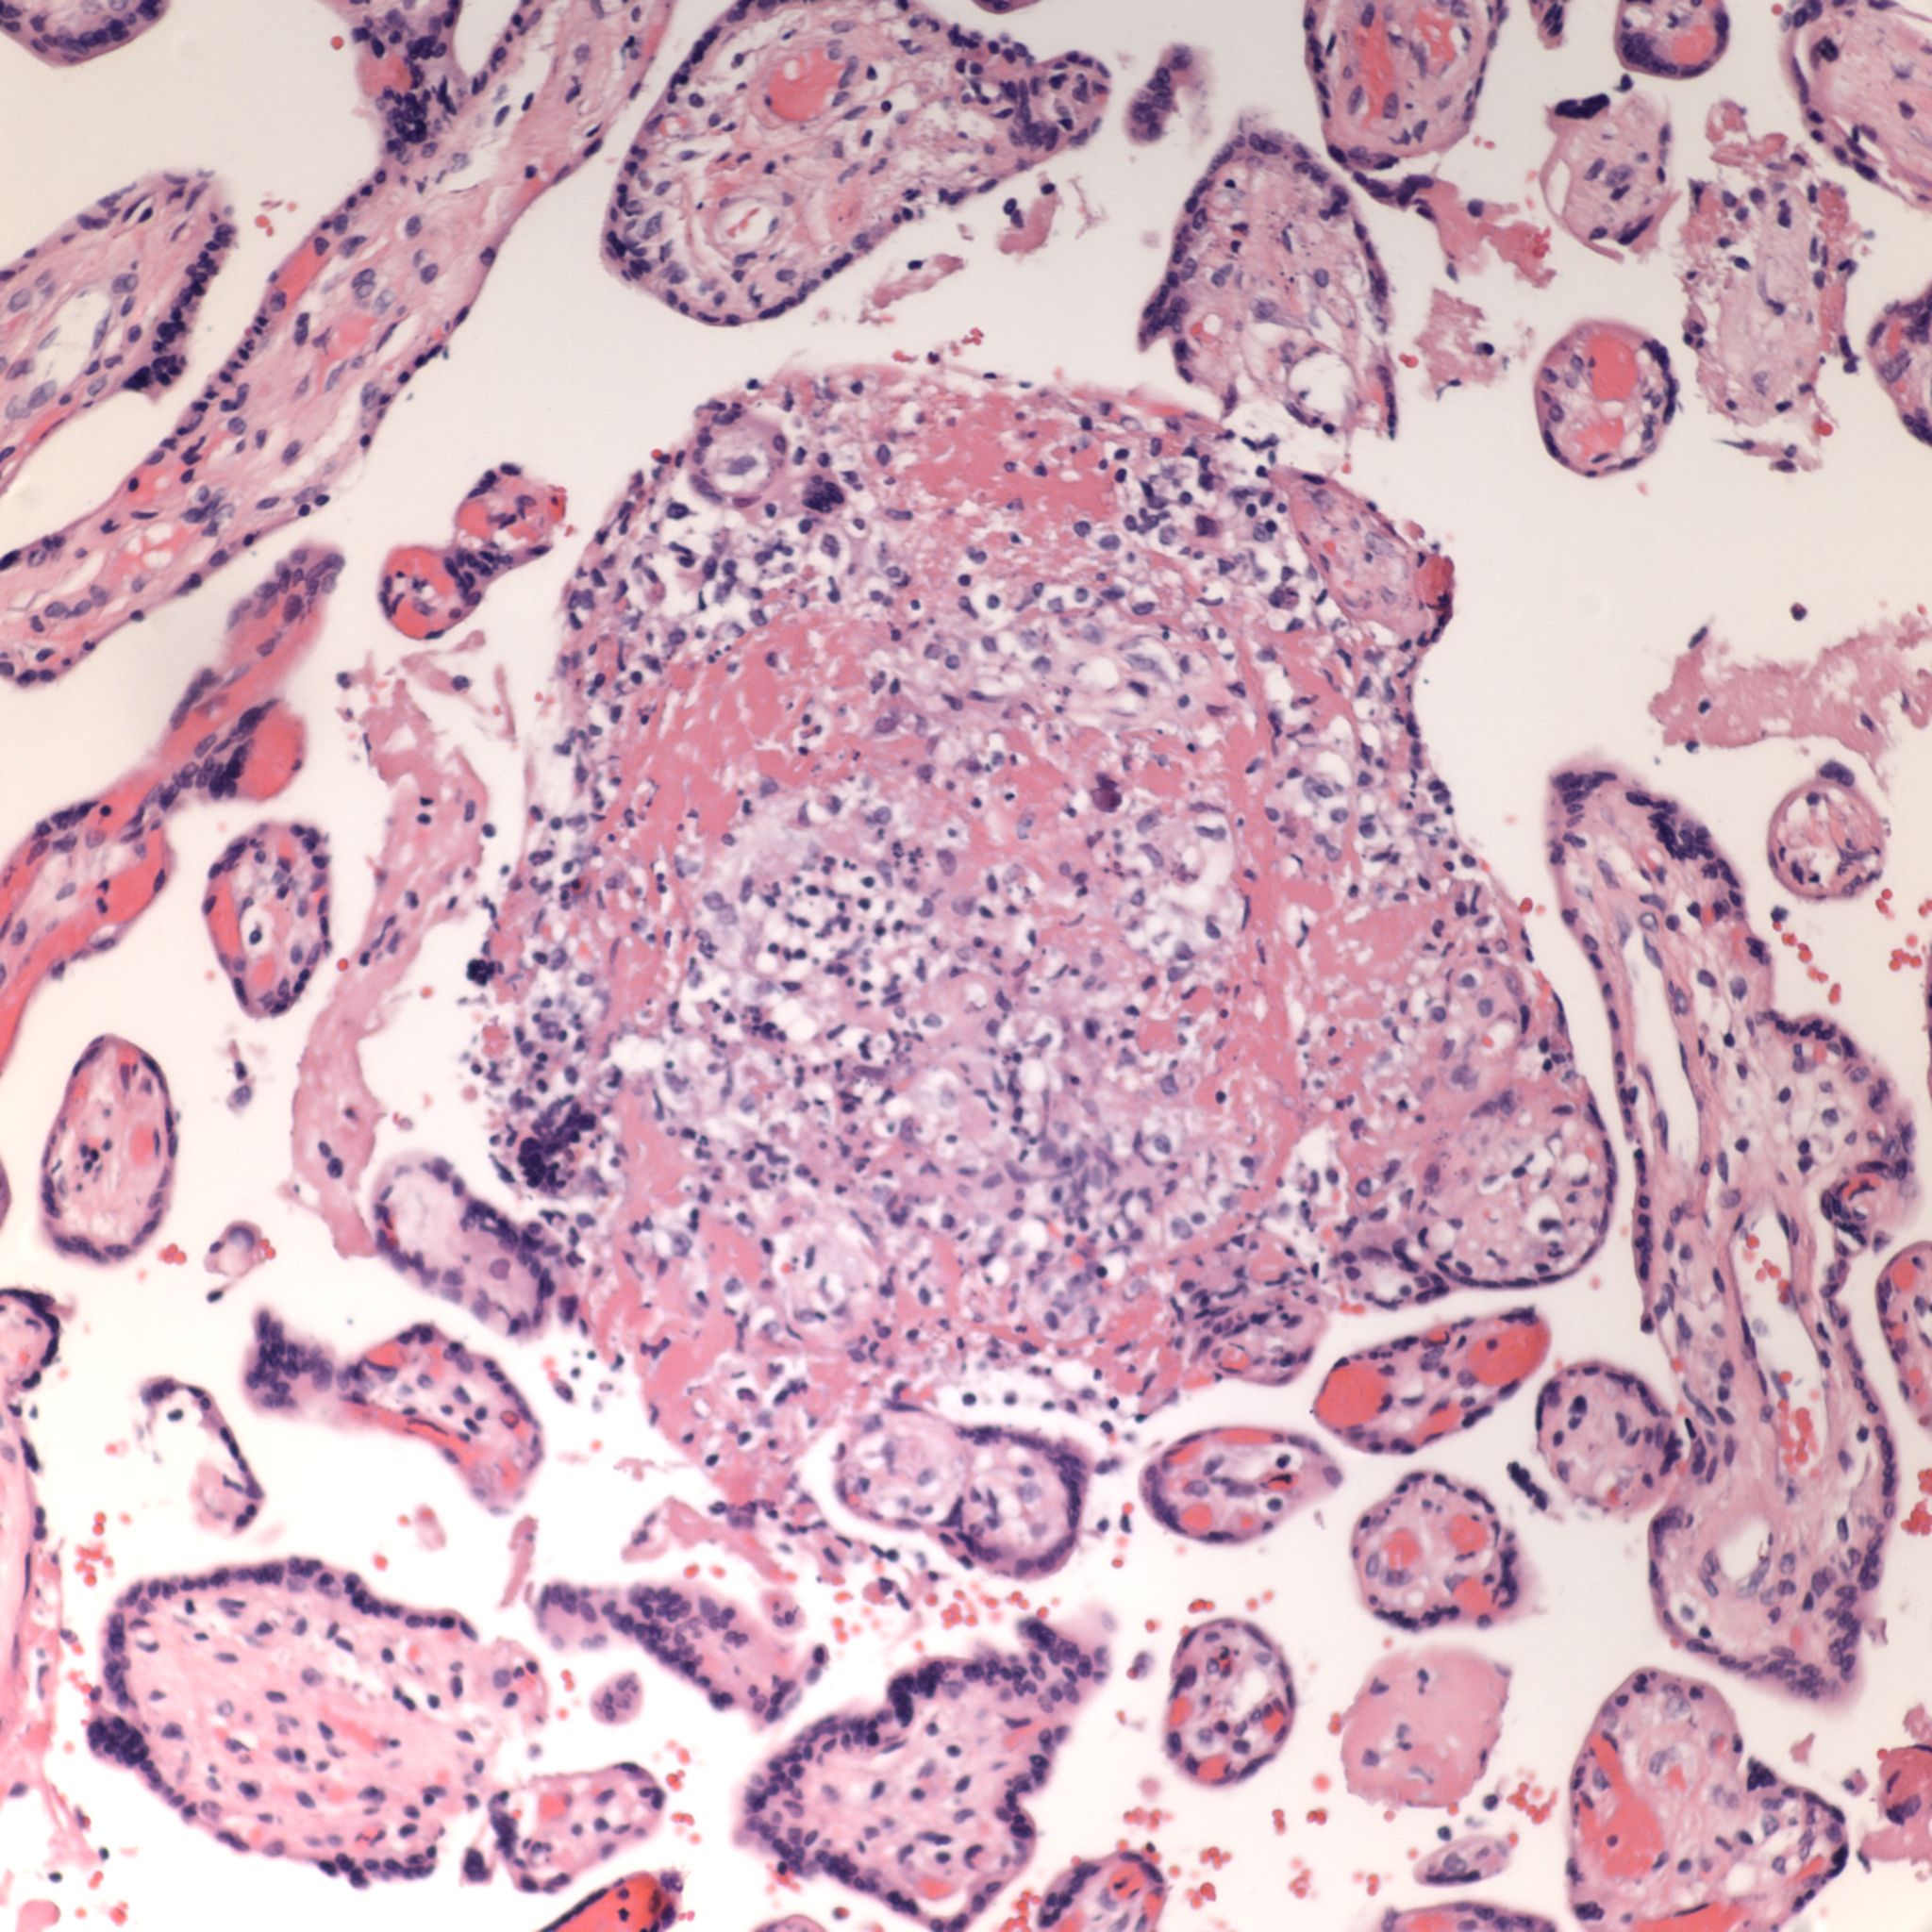

High Grade (massive) CHIV

Microscopic criteria: The primary criterion is monocytes clustered in the intervillous space which can be confirmed by CD 6810,17. The monocytes often have kidney bean shaped nuclei and prominent cytoplasm. Some other consensus criteria are that the inflammatory cells in the intervillous space should be at least 80% monocytes, and these should be maternal cells1,17.

Extent and Severity: If this is an untreated case, one accepted criterion is that the monocytes occupy 5% of the sampled intervillous space. The severity can also be graded usually as less than versus more than 50% of the intervillous space filled with monocytes. The number of monocytes in the largest clusters, and whether the distribution is evenly distributed or focal may also be useful observations.